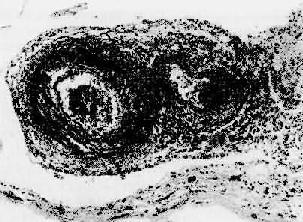

图4-13 结节性多动脉炎 两个动脉壁的各层都有炎性细胞浸润,外膜尤为显著。中膜发生纤维素样坏死 本病病变分布广泛,临床表现变异多端,患者常有低热、乏力、粒细胞增多以及多系统受累的症状,如血尿、肾功能衰竭、高血压、腹痛、腹泻、黑粪及周围神经炎等。病程快慢不一,经免疫抑制治疗,55%患者可存活。 病因与发病机制 病因和发病机制不明,动物实验提示,体液因素在本病的发生中起着重要作用。免疫荧光技术证实,人结节性多动脉炎血管壁中有免疫球蛋白和补体,有些还有HBsAg,约50%患者血清HBsAg或抗HBs阳性。 6.Wegener肉芽肿病 Wegener肉芽肿病是一种少见病,具有以下特点:①小血管急性坏死性脉管炎,可累有各器官的血管,以呼吸道、肾、脾最常受累。表现为小动脉、小静脉管壁的纤维素样坏死,伴弥漫性中性和嗜酸性粒细胞浸润;②呼吸道肉芽肿性坏死性病变,可累及口、鼻腔、鼻旁窦、喉、气管、支气管和肺。病变为由大量积集的单核巨噬细胞、淋巴细胞以及少量多核巨细胞、类上皮细胞、纤维母细胞组成的肉芽肿,中央可陷于成片凝固性坏死。肉眼常形成明显的肿块,表面则因坏死溃破而有溃疡形成;③坏死性肾小球肾炎,表现为在局灶性或弥漫增生性肾小球肾炎的基础上,有节段性毛细血管袢的纤维素样坏死,血栓形成,如未经治疗可发展为快速进行性肾炎,病程凶险,出现进行性肾功能衰竭。 本病的病因不明,由于有明显的血管炎,并于局部可检得免疫球蛋白和补体,提示其发病与Ⅲ型变态反应有关。但呼吸道出现的肉芽肿和坏死性病变,又提示可能与Ⅳ型变态反应有关,临床上应用细胞毒药物大多能使本病缓解。